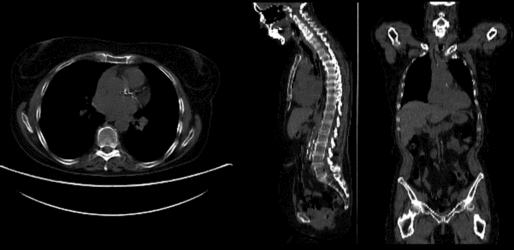

v3.6.3 Slicer3-6Announcement-v1.png Slicer Registration Library Case #20: Intra-subject whole-body PET-CT

this is the fixed PET/CT image. All images are aligned into this space lleft this is the moving image. The transform is calculated by matching this to the reference image

fixed image/target moving image